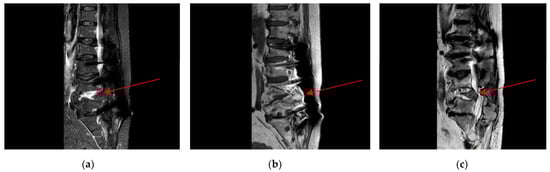

2.4. Neurosurgery Evaluation